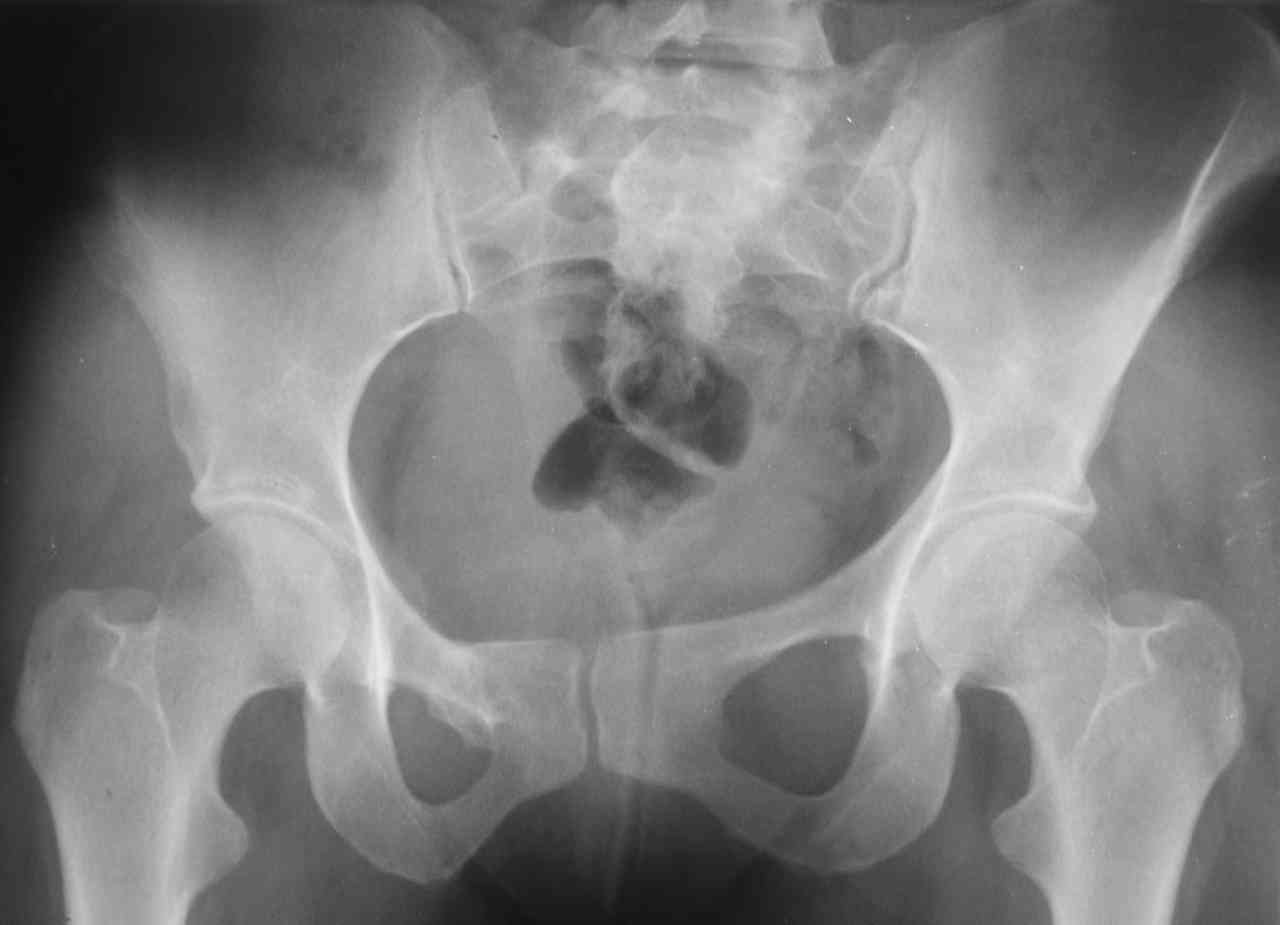

13/03/03 |  13/03/03 |  13/03/03 |  15/09/06 |  15/09/06 |  07/03/07 |  07/03/07 |  19/12/06 | К нам в клинику поступила пациентка 30 лет с диагнозом: Постравматическая ротационная стабильная деформация тазового кольца. Относительное укорочение левой н\конечности на 1 см. Левосторонний компенсаторный сколиоз 2 ст. Болевой синдром. травма автодорожная в январе 2003г. Пассажирка переднего сидения ваз 2109. лечились положением по Волковичу. С марта 2003 года жалуется на боли в тазу, ппояснице усиливающиеся при движении.В настоящее время жалобы на боли в области крестца, КПС больше слева, в пояснично-крестцовом отделе позвоночника. неприятные ощущения, щелчок при выпрямлении правого тазобедренного сустава из положения полного сгибания. боли в тазу появляются при ходьбе ч\з 100 м, так же при вставании из положения сидя, после сидения в течении 2-3 часов. при ходьбе более 100 м появпяется зябкость стоп больше справа. ходит при помощи трости в правой или в левой руке. без трости боли появляются сразу после начала ходьбы. пальпация болезненна в паравертебральных точках средне-грудного и пояснично-крестцового отделов позвоночника, КПС с обеих сторон. Объем движений в тазобедренных суставах полный.правый КПС заблокирован. симптомы натяжения с обеих сторон отрицательны.С 2003г. лечится консервативно, получала ЛФК, массаж, физиолечение - без эффекта. в 2005г. лечилась в санатории с ортопедическим уклоном, получала плавание в минеральной воде, магнитотерапия, массаж, ЛФК. отмечала умеренное улучшение в течении 2 недель.Вопросы:надо ли оперировать, т.е. устранять относительное укорочение левой н\конечности и как?Если не оперировать, то как лечить консервативно?Р-граммы, КТ прилогаются.

Уважаемый Алексей. Описанные Вами клинические проявления указывают на нестабильность левого крестцово-подвздошного сочленения. Такие больные встречаются не редко (за последние 6мес.в нашей клинике оперировано 3 больных со сроками давности от 6мес. до 1 года). К сожалению рентгенологически их трудно обьективизировать. На КТ это проявляется артрозом и костными разрастаниями КПС. В Вашем случае рентгенограммы и представленные томограммы ничего не дали. Можно попробовать посмотреть связочный аппарат КПС на МРТ хотя не уверен что Вы получите окончательный ответ. Если Вы будете убеждены в этом диагнозе то выход один костно-пластический артродез левого крестцово-подвздошного сочленения с фиксацией канюлированными шурупами. Заманчиво конечно и устранить ротационное смещение половины таза, но это на Ваше усмотрение.

почему она должна возникнуть? Сломан вроде крестец, хотелось бы посмотреть функциональные снимки таза.

Уважаемый Максим. Снимки от 7.03.07 и есть функциональные, т.е. стоя на правой, и левой ноге.